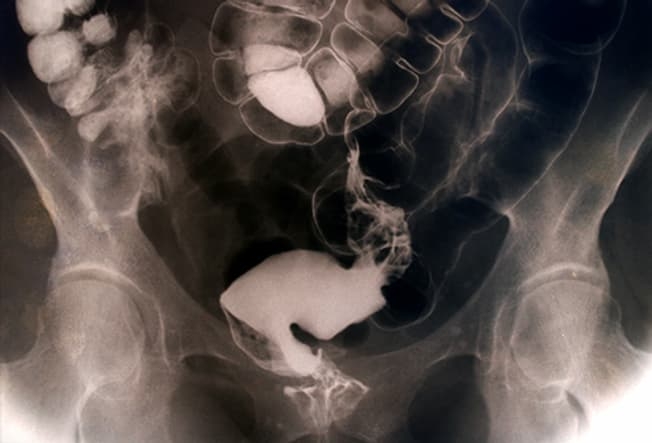

Когда это серьезно?

Большую часть времени мы можем справиться со вздутием самостоятельно. Но если вы испытываете слабость или потерю аппетита, или у вас диарея, потеря веса, лихорадка, боль в животе или кровь в стуле, поговорите с вашим врачом. Необходимо разобраться, что же происходит, врач возьмет образцы стула на анализ или назначит рентгенографию тонкого кишечника, или тесты не непереносимость лактозы или целиакию.